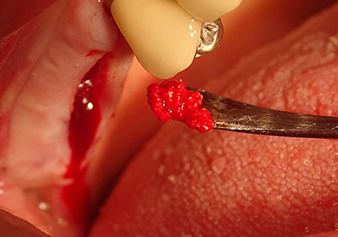

The I2A instrument (diameter 2.0 mm) was then used to perforate the sinus floor intermittently and on the smallest scale possible. This special piezosurgical method ensures that the Schneiderian membrane is not damaged. When the Z25P was used, the membrane was already lifted slightly by the coolant supplied via the instrument tip (Fig. 3). The coolant quantity was just 50% in order to avoid high pressure in the implant bed.

Implant bed preparation and augmentation

Following an intermediate check (Fig. 4) a further preparation step was performed (Fig. 5). Afterwards, the hydraulic Z35P instrument was used to lift the membrane to the desired position (Fig. 6 and 7). This was followed by further piezosurgical preparation of the implant bed, concluded with a rotary bur and shoulder milling cutter up to the implant diameter of 4.8 mm. Before the implant was inserted, the augmentation material (particle size approx. 0.8-1.6 mm) was introduced underneath the Schneiderian membrane (Fig. 8).